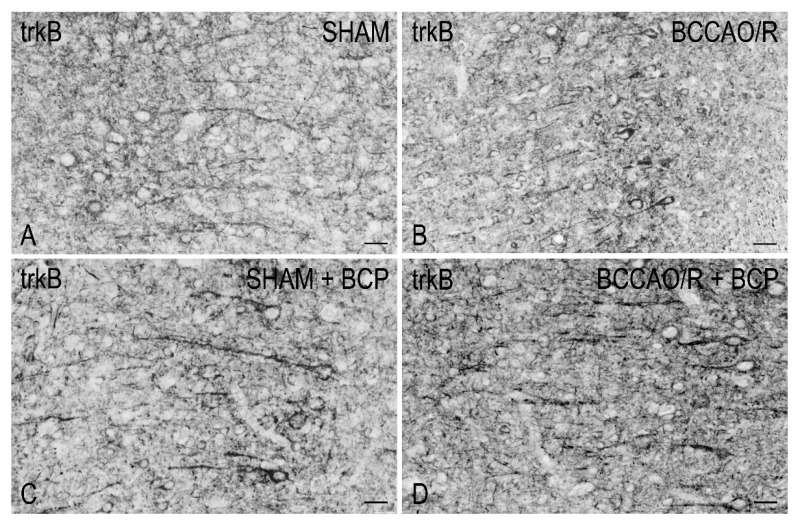

2.1.3. The trkB Protein Levels

The anti-trkB antibody, raised against the full-length isoform of the receptor protein, recognized a protein band with a relative mw of about 140 kDa (Figure 1), consistent with the reported mw of the receptor protein [ref. 57,ref. 58]. Assessment of the trkB densitometric values by a two-way ANOVA (Table 1) showed effects of the BCCAO/R (p < 0.0001) and of the BCP pre-treatment (p < 0.0001). Pair-wise contrasts revealed that, as a general rule, the BCP-treatment induced an increase of trkB relative levels amounting to about 97% (p = 0.0024) and 33% (p = 0.0028) in the sham-operated and BCCAO/R rats, respectively, vs. the vehicle-treated ones. In particular, in vehicle-treated animals, the trkB protein relative levels increased by 119% in BCCAO/R (p < 0.0001) vs. the sham-operated rats, while in the BCP-treated rats increased by 47% (p = 0.0002) in the BCCAO/R vs. the sham-operated.

To draw a parallel of the molecular changes observed by Western blot analysis with the tissue morphology, we performed immunostainings of the rat brain sections with the same antibodies used for Western Blot analysis. Immunoreactivities for all examined markers were localized to neuronal structures distributed throughout the rostro-caudal extension of the brain (Figure 3, Figure 4, Figure 5 and Figure 6). As regards the frontal cortex, TRPV1-LI appeared as sparse dot-like elements and tiny varicose nerve fibers distributed mostly close to blood vessels or around them (Figure 3 and Figure 6A,D,G). Neuronal perikarya showing a faint intracytoplasmic staining with a dust-like aspect were further detectable (Figure 6A,D). Labeling of the meningeal lining of the cortex was also detectable. By contrast with the scarcity of TRPV1-LI, the BDNF- and trkB-like immunoreactive structures were numerous and identifiable as neuronal perikarya and proximal processes and nerve fibers distributed throughout the cortical layers, having the aspect of loose networks of thin filaments and punctate elements in the superficial layers, and straight neuronal processes with a prevalent radial orientation in the deep layers (Figure 4 and Figure 5). Double labeling for either TRPV1 and GFAP (astrocyte marker) or TRPV1 and Iba1 (microglia marker), carried out by means of indirect immunofluorescence in selected series of brain sections from BCCAO/R rats showed that, in both BCP- and vehicle-treated rats, rare TRPV1-labelled nerve fibers and dot-like elements were also GFAP-immunoreactive (Figure 6C,F), whereas TRPV1/Iba1 colocalization was virtually absent (Figure 6B).

3.2. TRPV1-like Immunoreactive Structures in BCCAO/R with and without BCP

Similar to available studies on the distribution of TRPV1-LI in the rodent CNS [ref. 49,ref. 50], our results show that TRPV1 occurs in the frontal cortex where it localizes to cell bodies, mainly with an intracytoplasmic distribution, and dot- and thread-like elements suggestive of nerve fibers. However, at variance with previous studies [ref. 49,ref. 50], in our hands, the cortical TRPV1-labeling was light (under baseline and BCP-treated BCCAO/R conditions) to virtually absent (in BCCAO/R condition after vehicle-treatment) and, when present, the TRPV1-positive structures often underlined the course of some blood vessels in the cortex. It remains to clarify whether the vessel-associated immunoreactive elements we observed are genuine nerve fibers, as suggested by their varicose appearance, or stand for non-nervous vascular elements as shown by transmission electron microscopy (TEM) in the rat brain [ref. 49]. TRPV1 mRNA has also been reported in several other vascular beds in the rat [ref. 76,ref. 78]. Interestingly, the TRPV1 on sensory nerve terminals mediates local vasodilation, while the vascular TRPV1 leads to vasoconstriction [ref. 76]. Cavanaugh and coll [ref. 76] suggested that, in thermoregulatory tissues, activation of TRPV1 on vascular smooth muscle cells could counteract nerve-related changes in vascular tone in response to physiological TRPV1 agonists. Provided that a diverging role for TRPV1 was also possible in the brain vessels, it could be speculated that the TRPV1 increase induced by BCP in BCCAO/R compared to sham rats is partly involved in controlling the homeostasis of the cortical vascular bed under the reperfusion challenge.